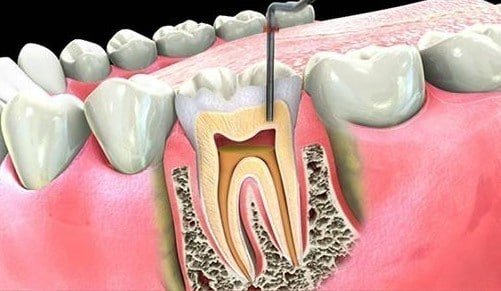

Florür etkilenen diş üzerine jel cila ya da macun şeklinde tatbik edilebilir.

Macunların kullanımı yanı sıra beslenmenize de özen göstermelisiniz. Kalsiyum deposu olan yumurta ile diş çürüklerini tedavi etmek mümkün. Uygulamak tamamen size kalmış olup kullanılan tedaviler kesin bir sonuç. Dişin iç pulpasını etkilemeyen diş minesindeki boşluklarda dolgu kullanılabilmektedir.